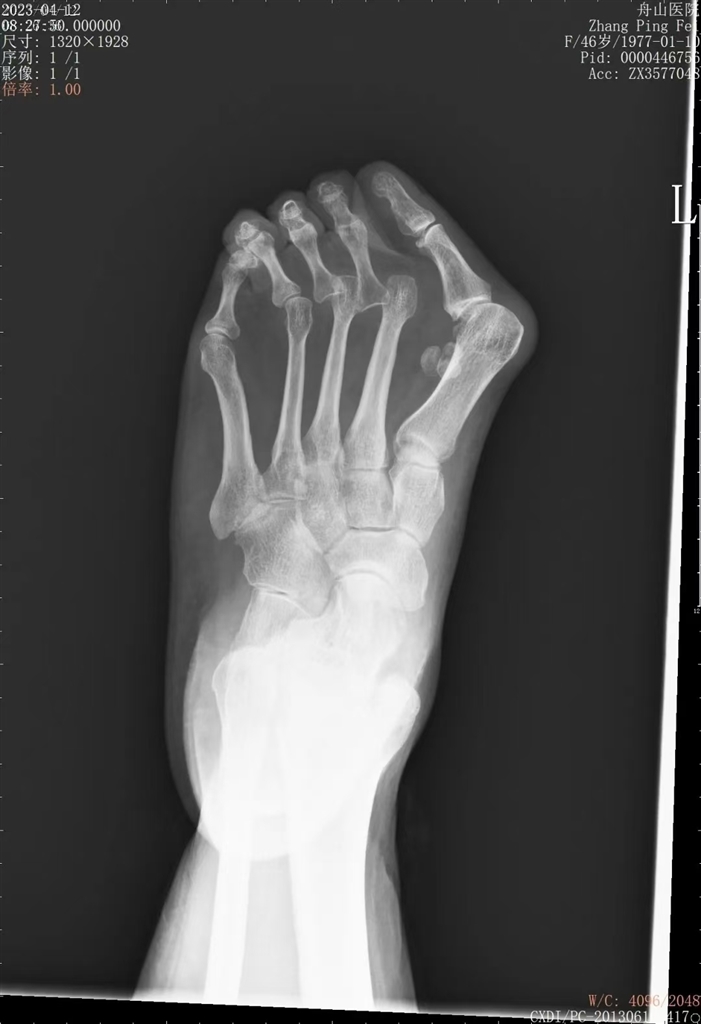

拇外翻手术前后

去年,舟山医院收治了一例严重拇外翻的女性患者。患者多年来一直有穿鞋尴尬,因为她两只脚的大脚趾都朝小脚趾倾斜,夏季就只能穿宽大的运动鞋或布鞋来遮挡。随着年龄增长,她走路时足部俞愈发疼痛,已严重影响正常生活,不得已到舟山医院就诊。

“这个患者的拇外翻已经发展得很严重了,除了拇趾,其他几个脚趾也出现了变形,第4趾还骑跨于第5趾,后来的手术就相对大一些。如果是轻度的拇外翻,是可以采用保守治疗的。”